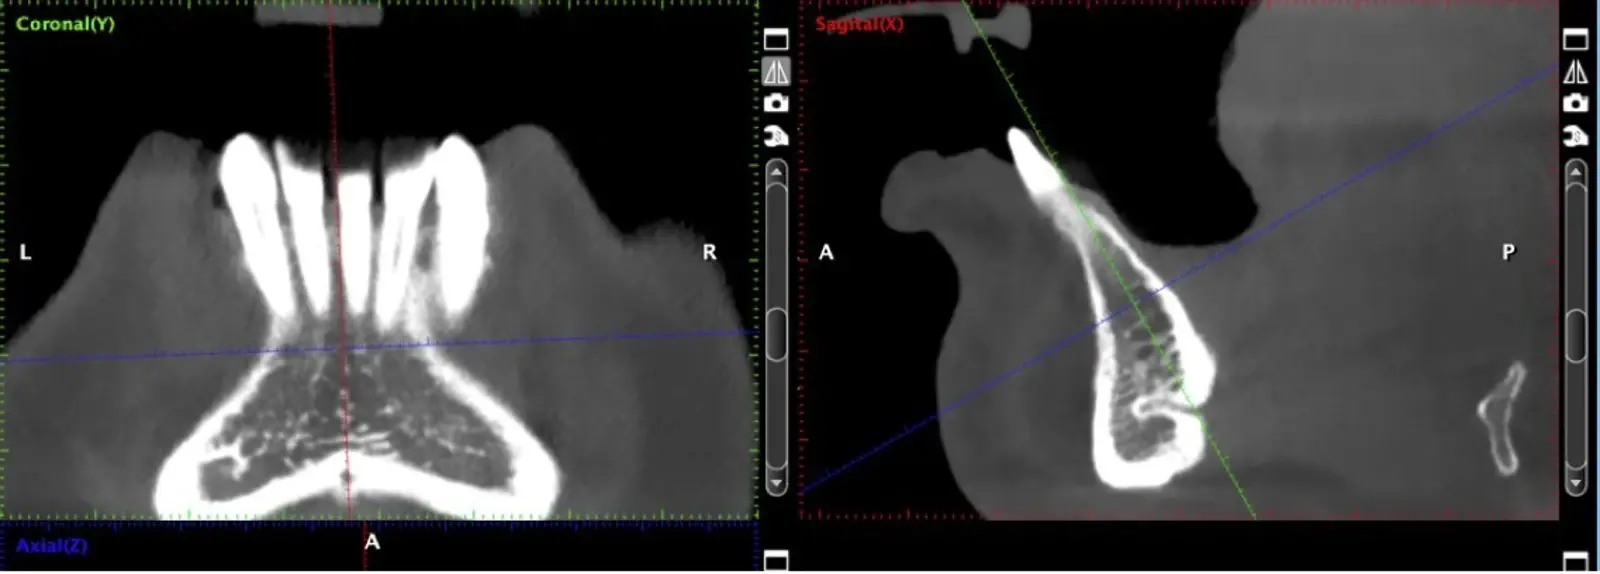

Figura 2. Evaluación de la tomografía computarizada donde se observa la presencia de un conducto vascular de riesgo a ser considerado.

Si la zona donadora es la rama mandibular, una vez realizado el decolado (Figura 4), se procede a realizar la osteotomía con los insertos de corte, según la accesibilidad se escoge el inserto angulado (Figura 5) o recto (Figura 6). Iniciamos con el corte horizontal que va desde la zona retromolar hacia mesial hasta unos 5 mm próximos a la última pieza dentaria, este corte se realiza con el inserto recto, luego se realizan osteotomías verticales. Finalmente, se realiza la osteotomía horizontal inferior con el inserto angulado del lado correspondiente, pero se debe determinar previamente en la tomografía la distancia al nervio dentario inferior, para evitar dañarlo por proximidad.